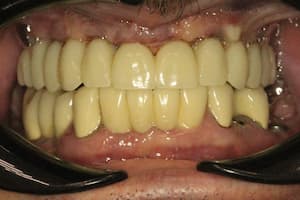

До

После

Удаление 7 зубов, установка 11 имплантов Straumann, временное и постоянное протезирование всех зубов с учетом формы, цвета и размера зубов. Работа с мягкими тканями. Импланты использовались для немедленной нагрузки.